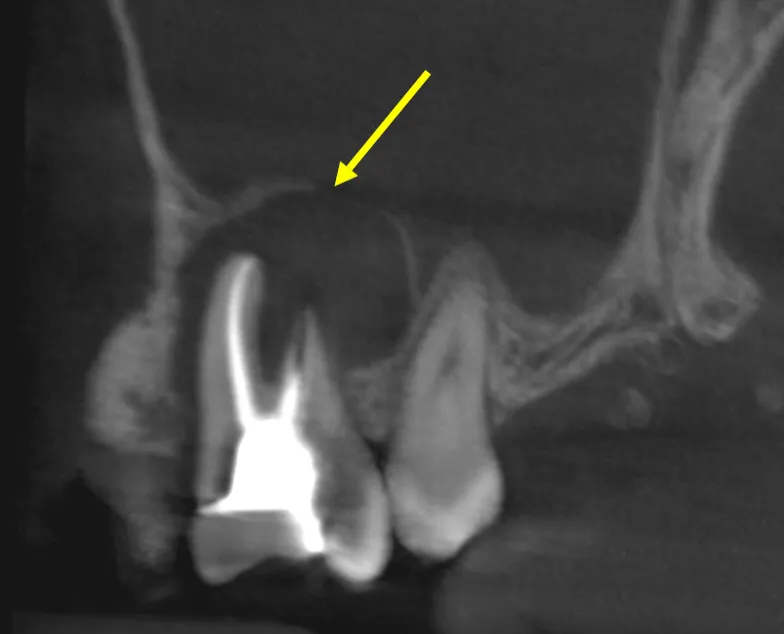

At 8 year follow-up, this tooth demonstrates excellent healing:

• Pocket depth reduced from 9mm to 4mm (clinically healthy)

• Radiographic bone regeneration visible around apex

• No symptoms, no swelling, no mobility

• Tooth fully functional in occlusion

Had we performed periodontal surgery first, the patient would have undergone unnecessary surgical trauma with likely poor results since the infection source (necrotic pulp) would have remained untreated.